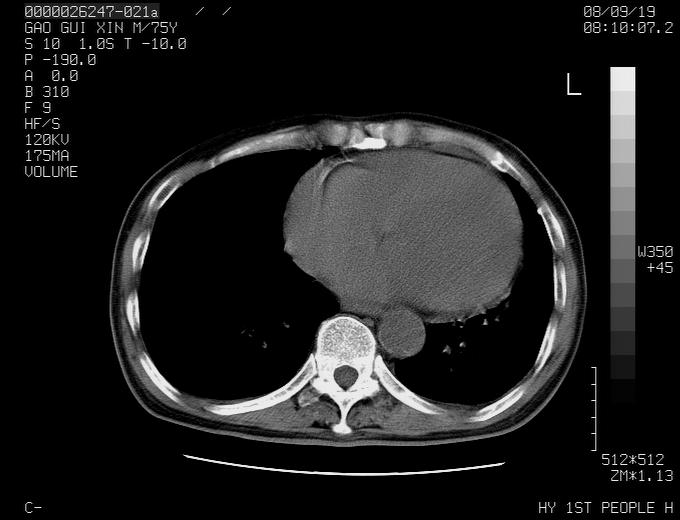

感谢各位老师的意见,左上肺病灶,我本人趋向结核,原因:左上肺见两个类圆形结节,仔细回顾4月份ct似乎原片在该处有条片状密度增高影,强化不明显。

右上肺可见条索状影,并可见钙化,左上肺结节可以考虑为结核球,但气管前腔静脉后有肿大淋巴结,本人觉得左上肺结节不能排除转移瘤的可能,右上肺为陈旧性结核灶。

双上肺继发型肺结核,纵隔淋巴结结核可能性大,建议定期复查.

1)左肺上叶尖段周围型肺癌并纵隔淋巴结转移。2)冠状动脉及主动脉钙化。